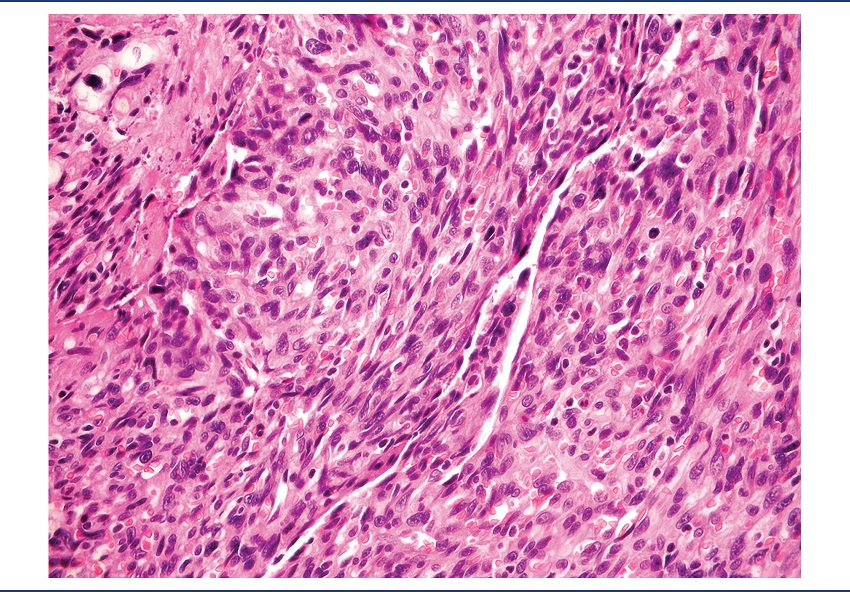

On pathological examination, the specimen was received fragmented, measuring 9.2 × 7 × 4 cm. There was a brownish nodule with hemorrhagic areas, measuring 4 cm in diameter, apparently infiltrating the cardiac wall (Figure 2). Microscopically, it was identified as a mesenchymal neoplasm, characterized by the proliferation of atypical endothelial cells with irregular nuclei, sometimes round sometimes spindle, without evident nucleolus, forming vascular spaces, papillae, and solid areas. Mitoses were frequent and necrosis was not observed. The lesion permeated cardiomyocytes, which presented clear cytoplasm and hypertrophic nucleus (Figures 3 to 7). There was infiltration of the visceral pericardium. The diagnosis was primary cardiac angiosarcoma.

HE: hematoxylin and eosin.

Histology can reveal different aspects, depending on the degree of differentiation. Well-differentiated areas are made by atypical pleomorphic endothelial cells, which form papillary structures or vascular channels. The poorly differentiated areas are formed by spindle anaplastic cells in solid pattern(7). The tumor presented both well-differentiated and poorly differentiated areas.